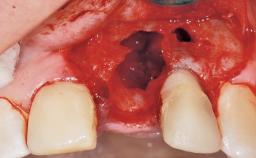

A 30-year-old female patient had lost tooth 21 and was referred to our clinic for consultation and treatment. Due to advanced apical infection, tooth 21 had been extracted two months earlier at another clinic and an acrylic-resin tooth had been bonded to the adjacent teeth. The patient desired implant treatment to avoid any damage to the adjacent natural teeth. While the patient had no history of any systemic disorder, she was a heavy smoker and exhibited medium to advanced periodontitis in the entire jaw. After the initial treatment to achieve a pocket probing depth of less than 4 mm and no bleeding on probing, a decrease in the height of the papillae mesial and distal to the extraction site and overall gingival recession were observed.

Bone Volume Horizontally and vertically sufficient Horizontally deficient Deficient vertically or deficient vertically AND horizontally

Bone Volume Deficient horizontally, requiring prior grafting